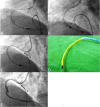

Figure 2

(A) Another 2.15 mm burr was also entrapped in the critical stenotic site and the Guideliner was used again. (B) Pushed the Guideliner catheter as well as simultaneously pulled the rotablator system, resulted in shortening the vessel but the burr still entrapped. (C) Successful retrieval of the entrapped burr using a 4 mm gooseneck snare combined with a Guideliner catheter. (D) A photograph of a 2.15 mm RotaLink Plus in the Guideliner catheter also with a snare. (E) Final angiogram.